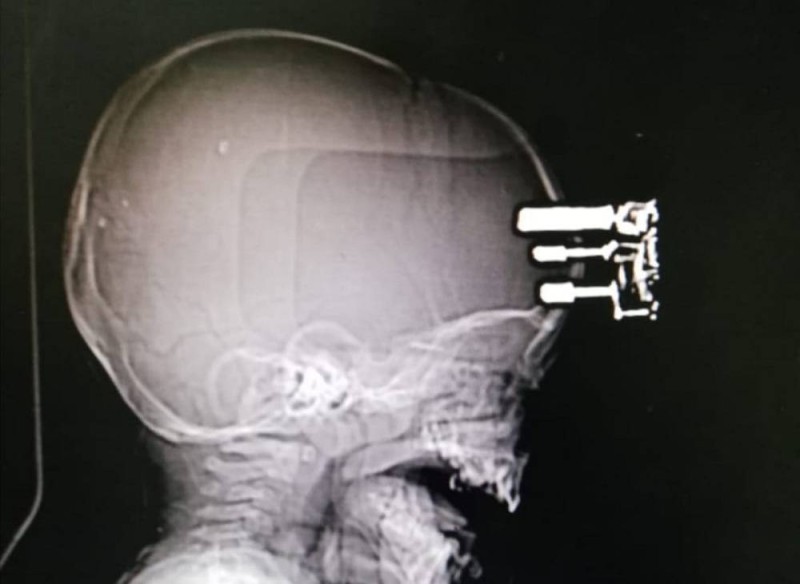

نجح فريق طبي بمستشفى الملك عبدالله في بيشة، في استخراج شاحن جوال من رأس طفل وإصلاح تلف أغشية الدماغ، إضافة إلى إصلاح كسر الجمجمة.

وفي التفاصيل، استقبل المستشفى حالة خطيرة بعد سقوط طفل يبلغ من العمر عاماً واحداً واصطدام رأسه بشاحن جوال على الأرض، ما أدى إلى اختراق أسنان الشاحن لعظم الجمجمة.

وجهز فريق طبي المريض وأجرى عملية مستعجلة استغرقت ساعتين منذ وصول المريض، وتمت بنجاح، ويتمتع الطفل بكامل وعيه ولا يعاني من أي قصور حركي أو أي مضاعفات.